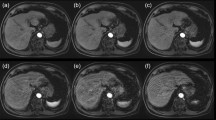

The dynamic contrast-enhanced acquisition used a fat-saturated T1-weighted radial stack-of-stars 3D GRE sequence with compressed-sensing and parallel-imaging reconstruction (GRASP) covering the entire liver with the following parameters: flip angle = 12°, repetition time ms/echo time = 4/2 ms, slice thickness = 2.5 mm, field of view = 384 × 384 mm, matrix = 288 × 288, in-plane resolution = 1.3 × 1.3 × 2.5 mm. The GRASP sequence was acquiring imaging raw data continuously for up to 270 s, starting with a 20-s non-contrast imaging phase prior to contrast-material administration and a subsequent contrast-enhanced imaging phase of up to 250 s. GRASP performs the continuous acquisition with a radial stack-of-stars k-space sampling scheme. This scheme enables retrospective reconstruction of image series with flexible temporal resolution by binning a certain number of consecutive spokes into individual time frames [14].

For this study, the image reconstruction used two sets of differing temporal k-space frames with each frame consisting of 5 spokes per frame for a 1st segment with 450 spokes, and, subsequently, of 34 spokes per frame for a 2nd segment until the end of the acquisition. The resulting temporal resolution of the reconstructed images from the dynamic scan was defined by the duration of each frame, which was 1 image per 1 s for the 1st segment, using batches of five spokes each, and of 1 image per 7 s for the 2nd segment, using batches of 34 spokes each. The 1st segment covered the time window relevant for our analysis with a total duration of 80 s, while the 2nd segment had various lengths, between 100 and 170 s, depending on the sequence’s final duration.

Superposed infographic map summarizing the cardiovascular contrast dynamic, the hepatic translational activities, and the diaphragmatic plethysmography during the contrast-enhanced MRI of the liver following administration of gadoxetate (a) and gadoterate (b), in two different patients. The relative cardiovascular intensity values normalized based on the initial 20-s acquisition extracted from right-ventricular (dark red), left-ventricular (red), and aortic (light red) ROIs plotted over time allow individual definition of eight time points throughout the election cycle (upper graph); temporal evolution is 1 s. The relative hepatic intensity values were derived from the hepatic ROI (green), plotted over time; temporal resolution is 1 s. A hepatic displacement implying a transient respiratory motion beyond normal breathing motion was considered to be significant when a variation of the signal intensity of at least two standard deviations from the baseline was observed. The extracted plethysmographic curve (gray) with a temporal resolution of 0.19 s is superimposed onto the hepatic intensity curve (lower graph). Pronounced respiratory irregularity is seen during the early arterial contrast phase for gadoxetate (a) and during the peripheral venous phase for gadoterate (b), both resulting in extensive hepatic translational movement. Transient respiratory motion occurring after administration of gadoterate (b) is outside the acquisition window for arterial phase MR imaging (black box) while gadoxetate (a) administration leads to motion during the crucial early arterial MR imaging phase

Evaluation of cardiovascular contrast dynamics

Each four-dimensional dataset was loaded into the software application and reformatted into the axial and coronal image planes. Three regions-of-interest (ROIs) were placed manually: within the central right and left ventricles, and within the lumen of the abdominal aorta immediately upstream from the origin of the celiac trunk. The resulting intensity values were normalized and plotted over time as presented in Fig. 2. These cardiovascular intensity curves resulted in eight intra-individually defined contrast phases: Tbaseline (first 20 s of the acquisition), Tperipheral-venous (peripheral-venous distribution starting at the 20-s mark until right-ventricular maximum intensity), Tpulmonary (pulmonary distribution ranging from right-ventricular to left-ventricular intensity maxima), Taortic (aortic distribution ranging from left-ventricular to aortic maxima), Tearly-arterial and Tlate-arterial (hepatic arterial parenchymal distribution during two consecutive 20-s intervals starting at maximum aortic intensity), Tportal venous (portal venous parenchymal distribution from 40 to 90 s after maximum aortic intensity), and finally Tdelayed (contrast distribution from 90 s after maximum aortic intensity up to the end of the acquisition). The first four contrast phases will be referred to as the pre-bolus phase.

Evaluation of respiratory-induced translation of the liver

Each four-dimensional image set was reformatted to the coronal plane for evaluation of hepatic cranio-caudal translation due to respiration. A crescent-shaped polygonal ROI was placed just below the diaphragm within hepatic segment VIII during expiration-induced buckling of the right diaphragm. The intensity values were normalized and plotted over time. Hepatic translation was represented by decreasing signal intensities as seen in Fig. 2.